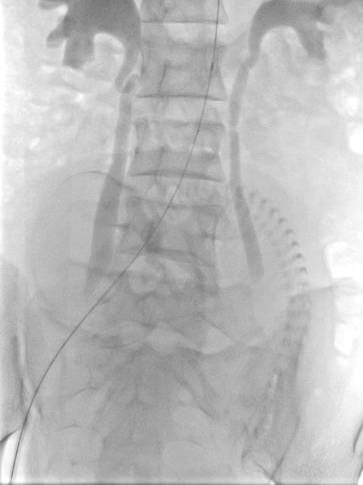

当双侧的子宫动脉栓塞结束后,小BABY已经没有了胎动,说到这读者应该明白是怎么回事了,凶险型前置胎盘伴胎盘植入者剖宫产术中平均出血量高达3000~5000 ml,甚至高达10000 ml以上,严重威胁孕产妇生命安全。既往凶险性前置胎盘剖宫产术后为止血而切除子宫,术中平均失血量仍达为3000-5000ml。为减少出血保留子宫,产科以往采取结扎髂内动脉或子宫动脉,然而对于凶险性前置胎盘并伴有胎盘植入的患者,即使结扎髂内或子宫动脉,也无法完全阻断胎盘植入部位的血供,并且剖宫产术中因出血量大,行髂内或子宫动脉结扎难度增大。近年来球囊导管技术已越来越多的应用于凶险型前置胎盘伴胎盘植入剖宫产术。由于孩子太大避免手术出血过多介入科医生在腹主动脉双侧肾动脉下方放置了球囊导管阻断腹主动脉下端的血供图二。

图二:球囊导管置入

图二:猪尾导管造影定位